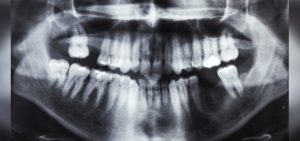

Un niño se quejaba de un fuerte dolor en la boca, por lo que decidió acudir al hospital Saveetha Dental College ubicado en Chennai, India. Al concluir la inspección se le realizó una radiografía y una tomografía, saliendo a la luz la existencia de más de 500 dientes en su boca.

El niño tenía una «estructura en forma de bolsa» en la boca, la tomografía reveló múltiples dientes rudimentarios. La situación del menor requirió cirugía, la cual duró más de 5 horas con un resultado favorable.

Al término del procedimiento quirúrgico el pequeño se quedó con 21 dientes, su caso será estudiado minuciosamente para saber las causas.